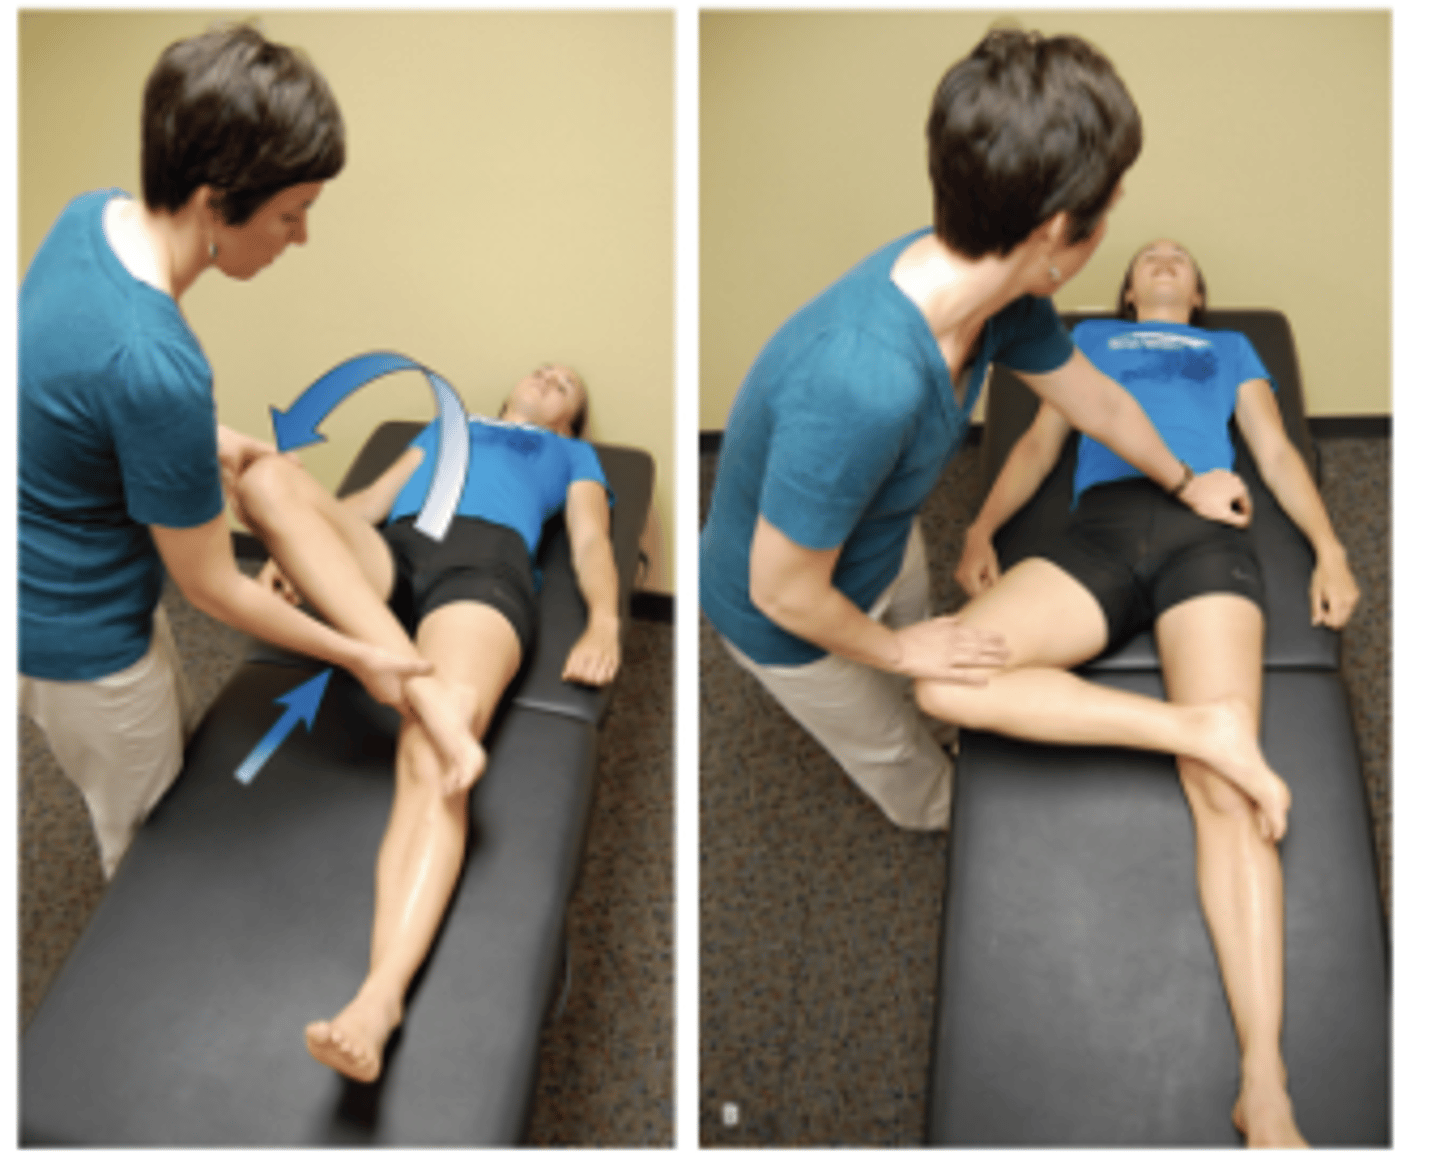

Log Roll

Tests for: FAI, labral injury, generalized laxity